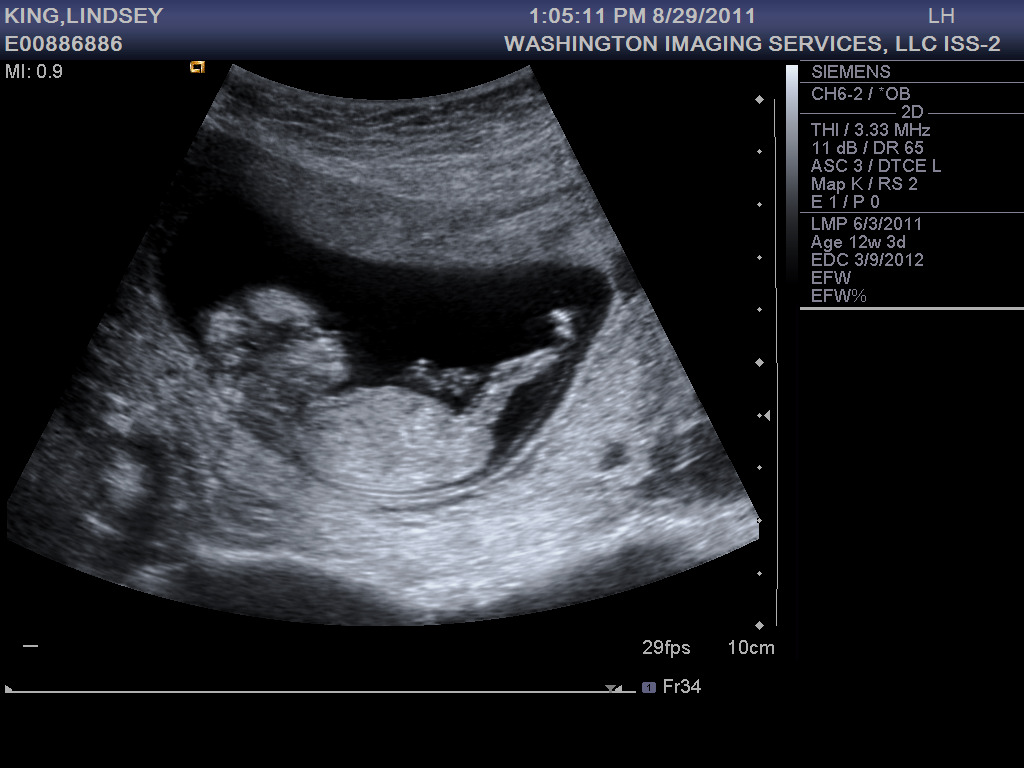

At my ultrasound last week, baby #3 was 13 weeks along and looking healthy and active. He or she was moving around so much the tech had to work extra hard to get measurements. Is this an indication of what to expect later on?

The first trimester is behind me now, thank goodness. So far I’m still exhausted and nauseous, but I expect these symptoms to wane in the coming weeks. Did I mention how T-I-R-E-D I’ve been? By 2pm I just want to crawl into bed in the fetal position, but there are still hours left until Jonathan’s home, then there’s dinner, putting the boys to bed, and by the time we finally hit the hay, I can’t fall asleep! So I toss and turn like a rotisserie chicken until at last sleep comes. But even then I wake up several times in the night, never really getting that sweet REM sleep… and then it’s time to get up and do it all over again. Okay, I’ll stop complaining now. I had it easy the first two times around, I should be thankful. And really, it could be a lot worse. On the up side, I get to spend my days with the two sweetest little boys in the world!

13 week bump shot